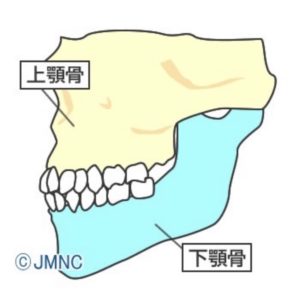

②外科矯正

外科矯正とは通常の歯列矯正と外科手術を組み合わせたものです。

上顎・下顎の形や位置関係に問題があることが原因で不正咬合になっている場合は

「顎変形症」と診断されて、顎の位置や形を整える外科手術が適応となります。

手術前矯正→顎矯正手術→手術後矯正という流れで保険が適応となります。

全身麻酔下での外科手術・2~3週間の入院が必要となりますが

顎の位置から変わるため噛み合わせやお顔の印象が大きく変化します。